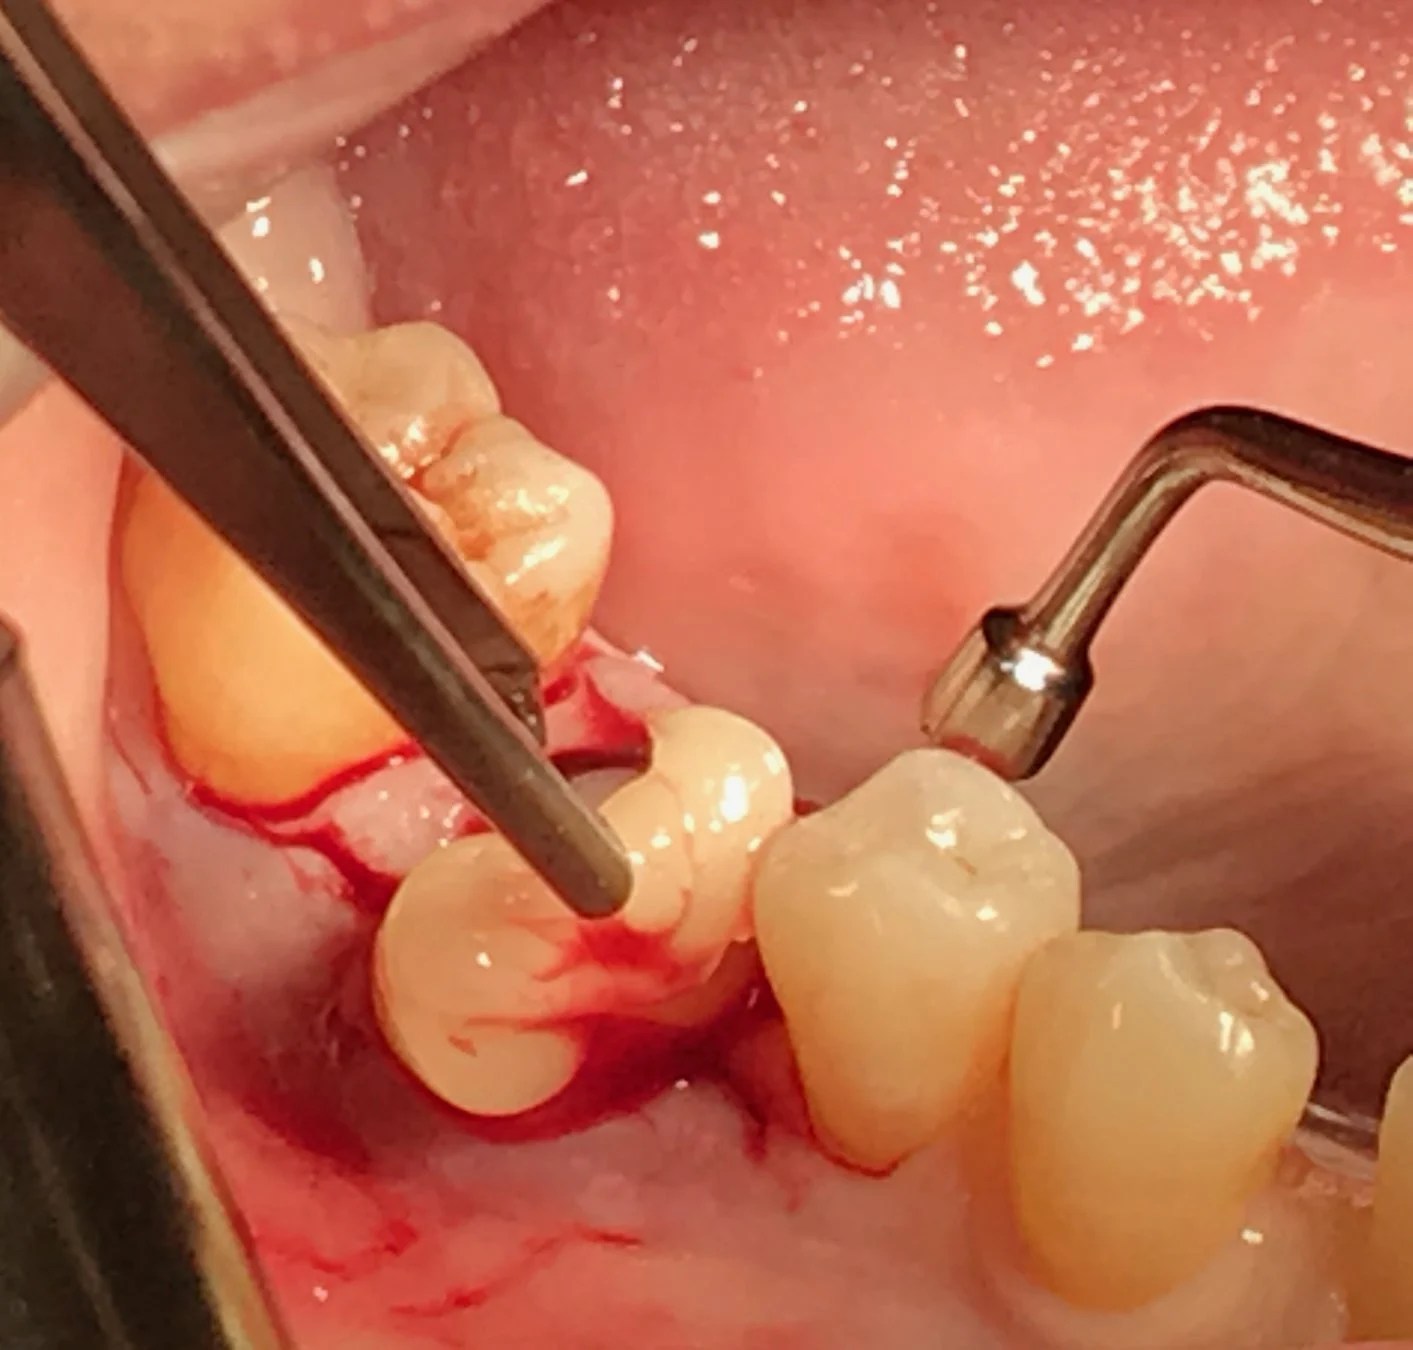

From burnsdentistry.com

PRP/PRF Burns Dentistry Dental Prf Code One of the latest innovations in oral surgery is the use of platelet concentrates for in vivo tissue engineering applications: Insurance reimbursement may be available utilizing cpt code 7921—collection and application of autologous blood concentrate product. Listing of a code in. The following list(s) of procedure and/or diagnosis codes is provided for reference purposes only and may not be all. Dental Prf Code.

From sacramentonaturaldentistry.com